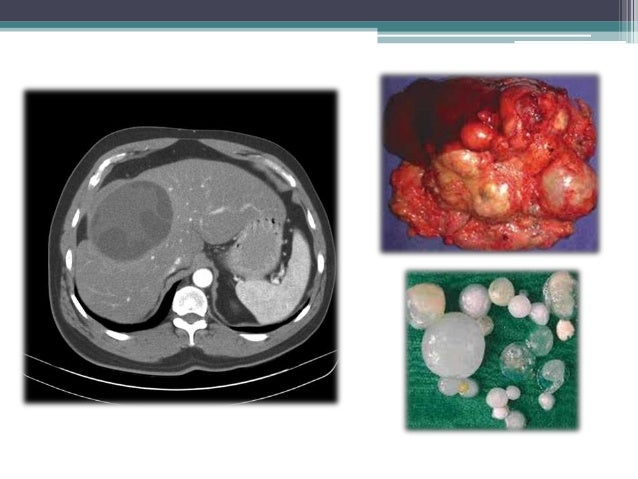

Manifestaciones Clínicas:

Dependen de la localización y del

tamaño del quiste. Las localizaciones más frecuentes son: hígado, pulmón,

riñón, mesenterio y peritoneo, también se puede ubicar en sistema nervioso,

músculos, huesos, etc.

Métodos de Diagnostico:

Inmunológico:

ELISA, HI, Prueba de Casoni.

Radiológico:

Rx simples, Ecosonografía, RM.

Parasitológico:

Observación de los componentes del quiste en material eliminado espontáneamente

u obtenido por cirugía, teñidas con hematoxilina-eosina y PAS.